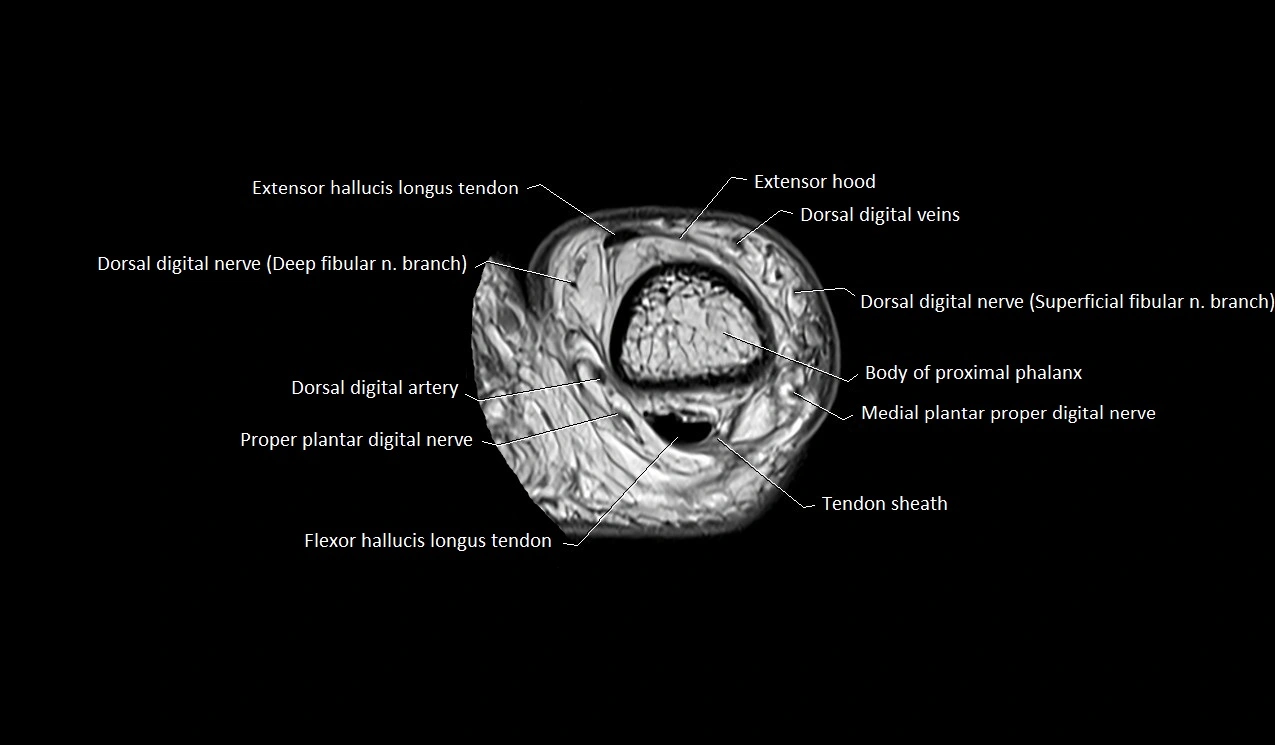

MRI image

image